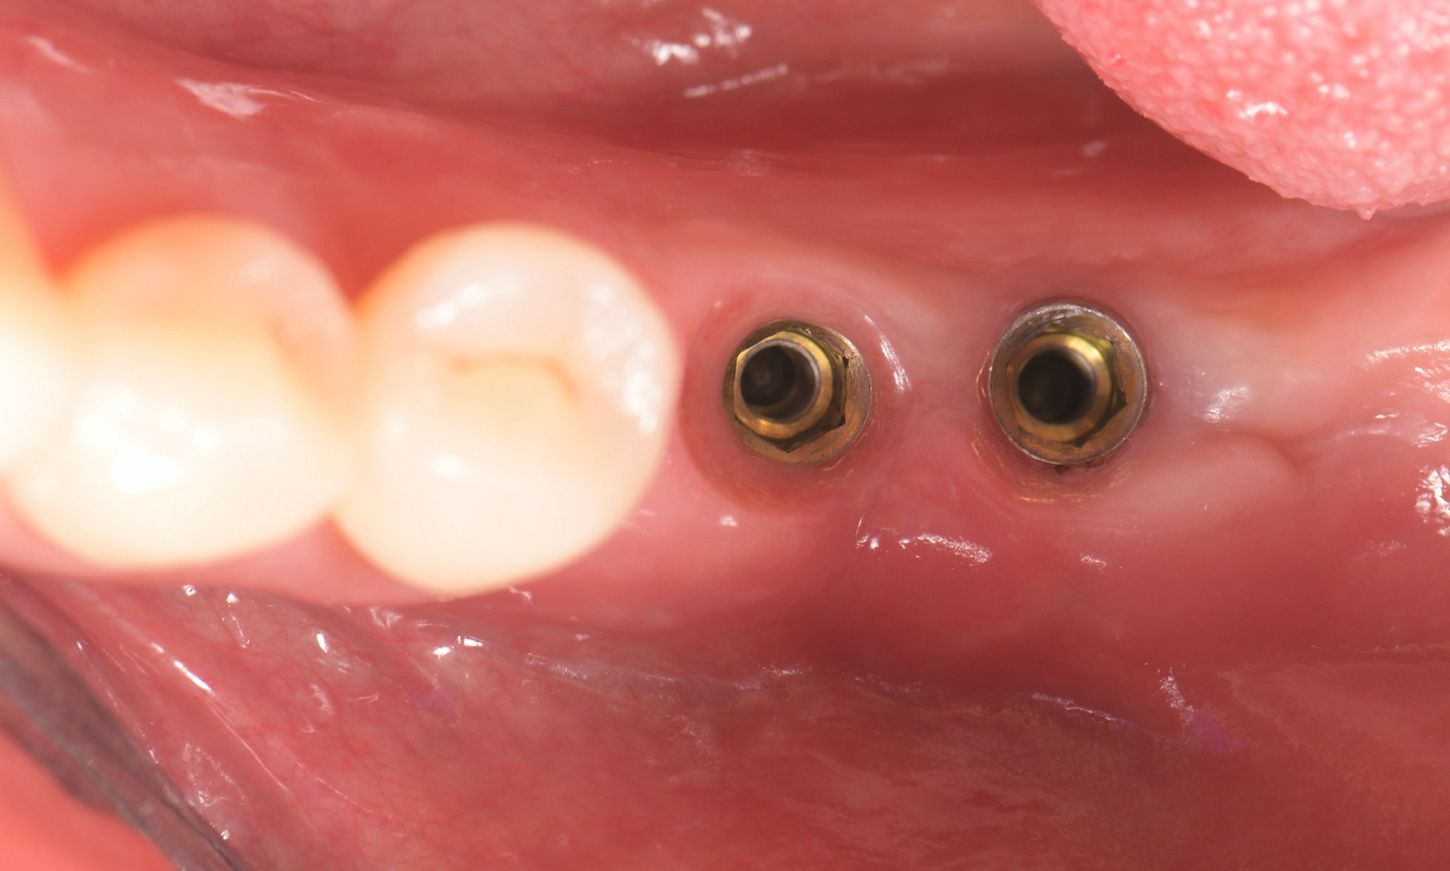

In 2021, six months after the initial surgery, a full-thickness flap was elevated, revealing that the implants were surrounded by bone (Figs. 14,15). Healing abutments were then inserted, and interrupted sutures were inserted using 6/0 prolene (Fig. 16). The healing abutments play an essential role in facilitating proper healing of the gingival tissue around the implant, shaping the tissue for an optimal fit of the final prosthesis, and protecting the implant from contaminants.